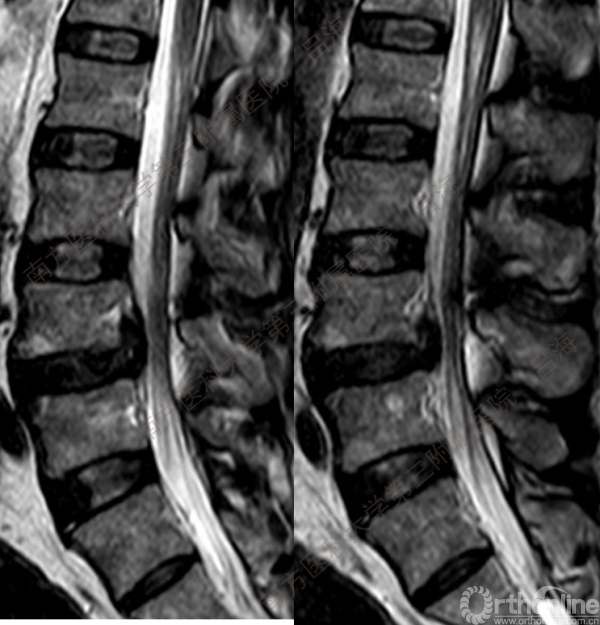

随着社会老龄化进程加快,胸腰椎退行性病变的治疗已经成为脊柱学术界的一个热点话题。MIS-TLIF手术可以治疗多种不同的胸腰椎退行性疾病,南方医科大学第三附属医院吕海教授结合病例为我们一一展示了该术式在治疗不同胸腰椎疾病时的具体手术过程。